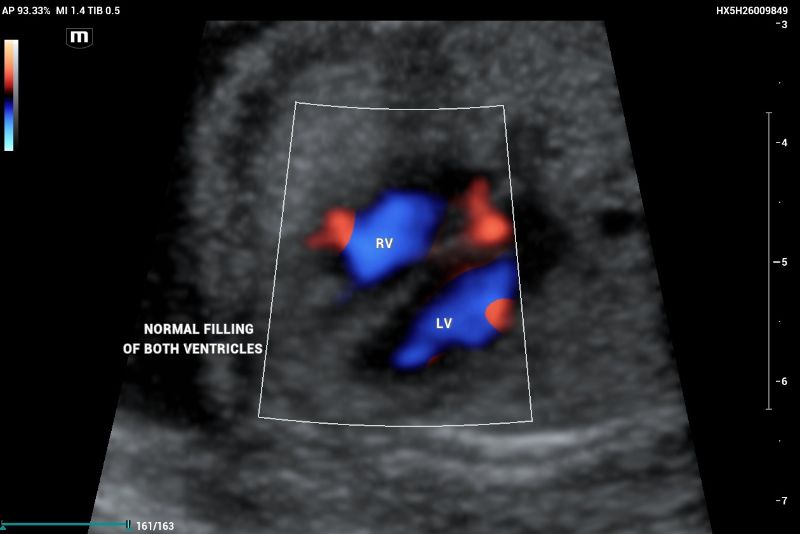

According to the ISUOG 2023 guidelines, second-trimester screening includes a standardized protocol for anatomical evaluation, incorporating fetal echocardiography. In a normal fetal echocardiogram, the ventricles should be symmetric and of equivalent size; any asymmetry is suggestive of disease (figure 1, and 2).

An example of normal echocardiography ultrasound screening showing Right ventricle (RV) and Left ventricle with normal filling

Figure 2. An example of normal echocardiography ultrasound screening showing Right ventricle (RV) and Left ventricle with normal filling.